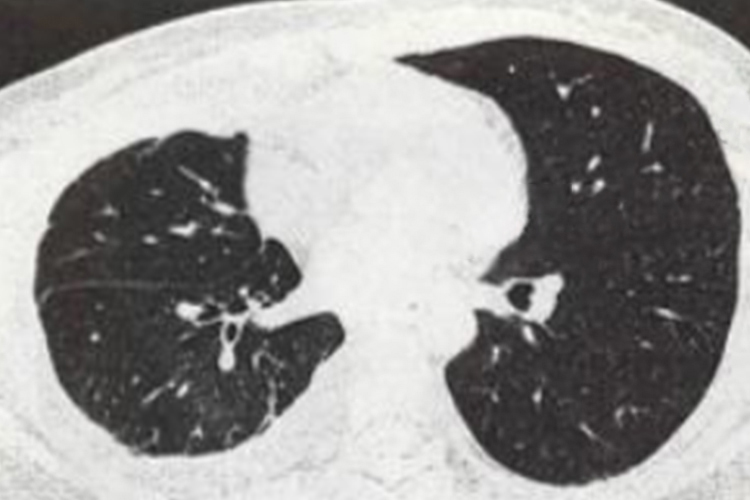

肺部大面积感染是否可以治疗成功主要取决于多个因素,包括感染的类型、患者的年龄、身体状况、是否存在其他并发症,以及治疗的及时性和有效性等。

- 如果患者年龄较轻、身体状况较好,即使是肺部大面积感染,通过使用有效的药物和其他治疗方法也能达到比较满意的效果,大多数患者能够治愈。对于细菌感染,遵医嘱选择敏感的抗生素可以有效缓解炎症反应。结核分枝杆菌感染可以在医生指导下通过联合使用多种抗结核药物来治疗。

- 如果患者出现呼吸衰竭、肺部萎缩、休克等现象,或者伴有肾功能不全等并发症,可能会危及生命。年龄较大或身体条件较差的患者,尤其是存在耐药菌感染的情况下,治疗效果可能不佳。

- 对于部分免疫系统疾病患者,如艾滋病患者,其免疫系统功能受损,感染可能较为严重且难以控制。这类患者需要更加全面的治疗和护理。根据病情需要,可能还需要进行氧疗、呼吸机支持等生命器官支持治疗。

肺部大面积感染在大部分情况下是可以治疗的,但治疗的成功与否取决于上述因素。重要的是要尽早寻求医疗帮助,接受�适当的诊断和治疗。医生会根据患者的具体情况制定个性化的治疗计划。在治疗过程中,患者也需要积极配合,保持良好的生活习惯,按时服药并定期复查,以提高治疗成功的可能性。